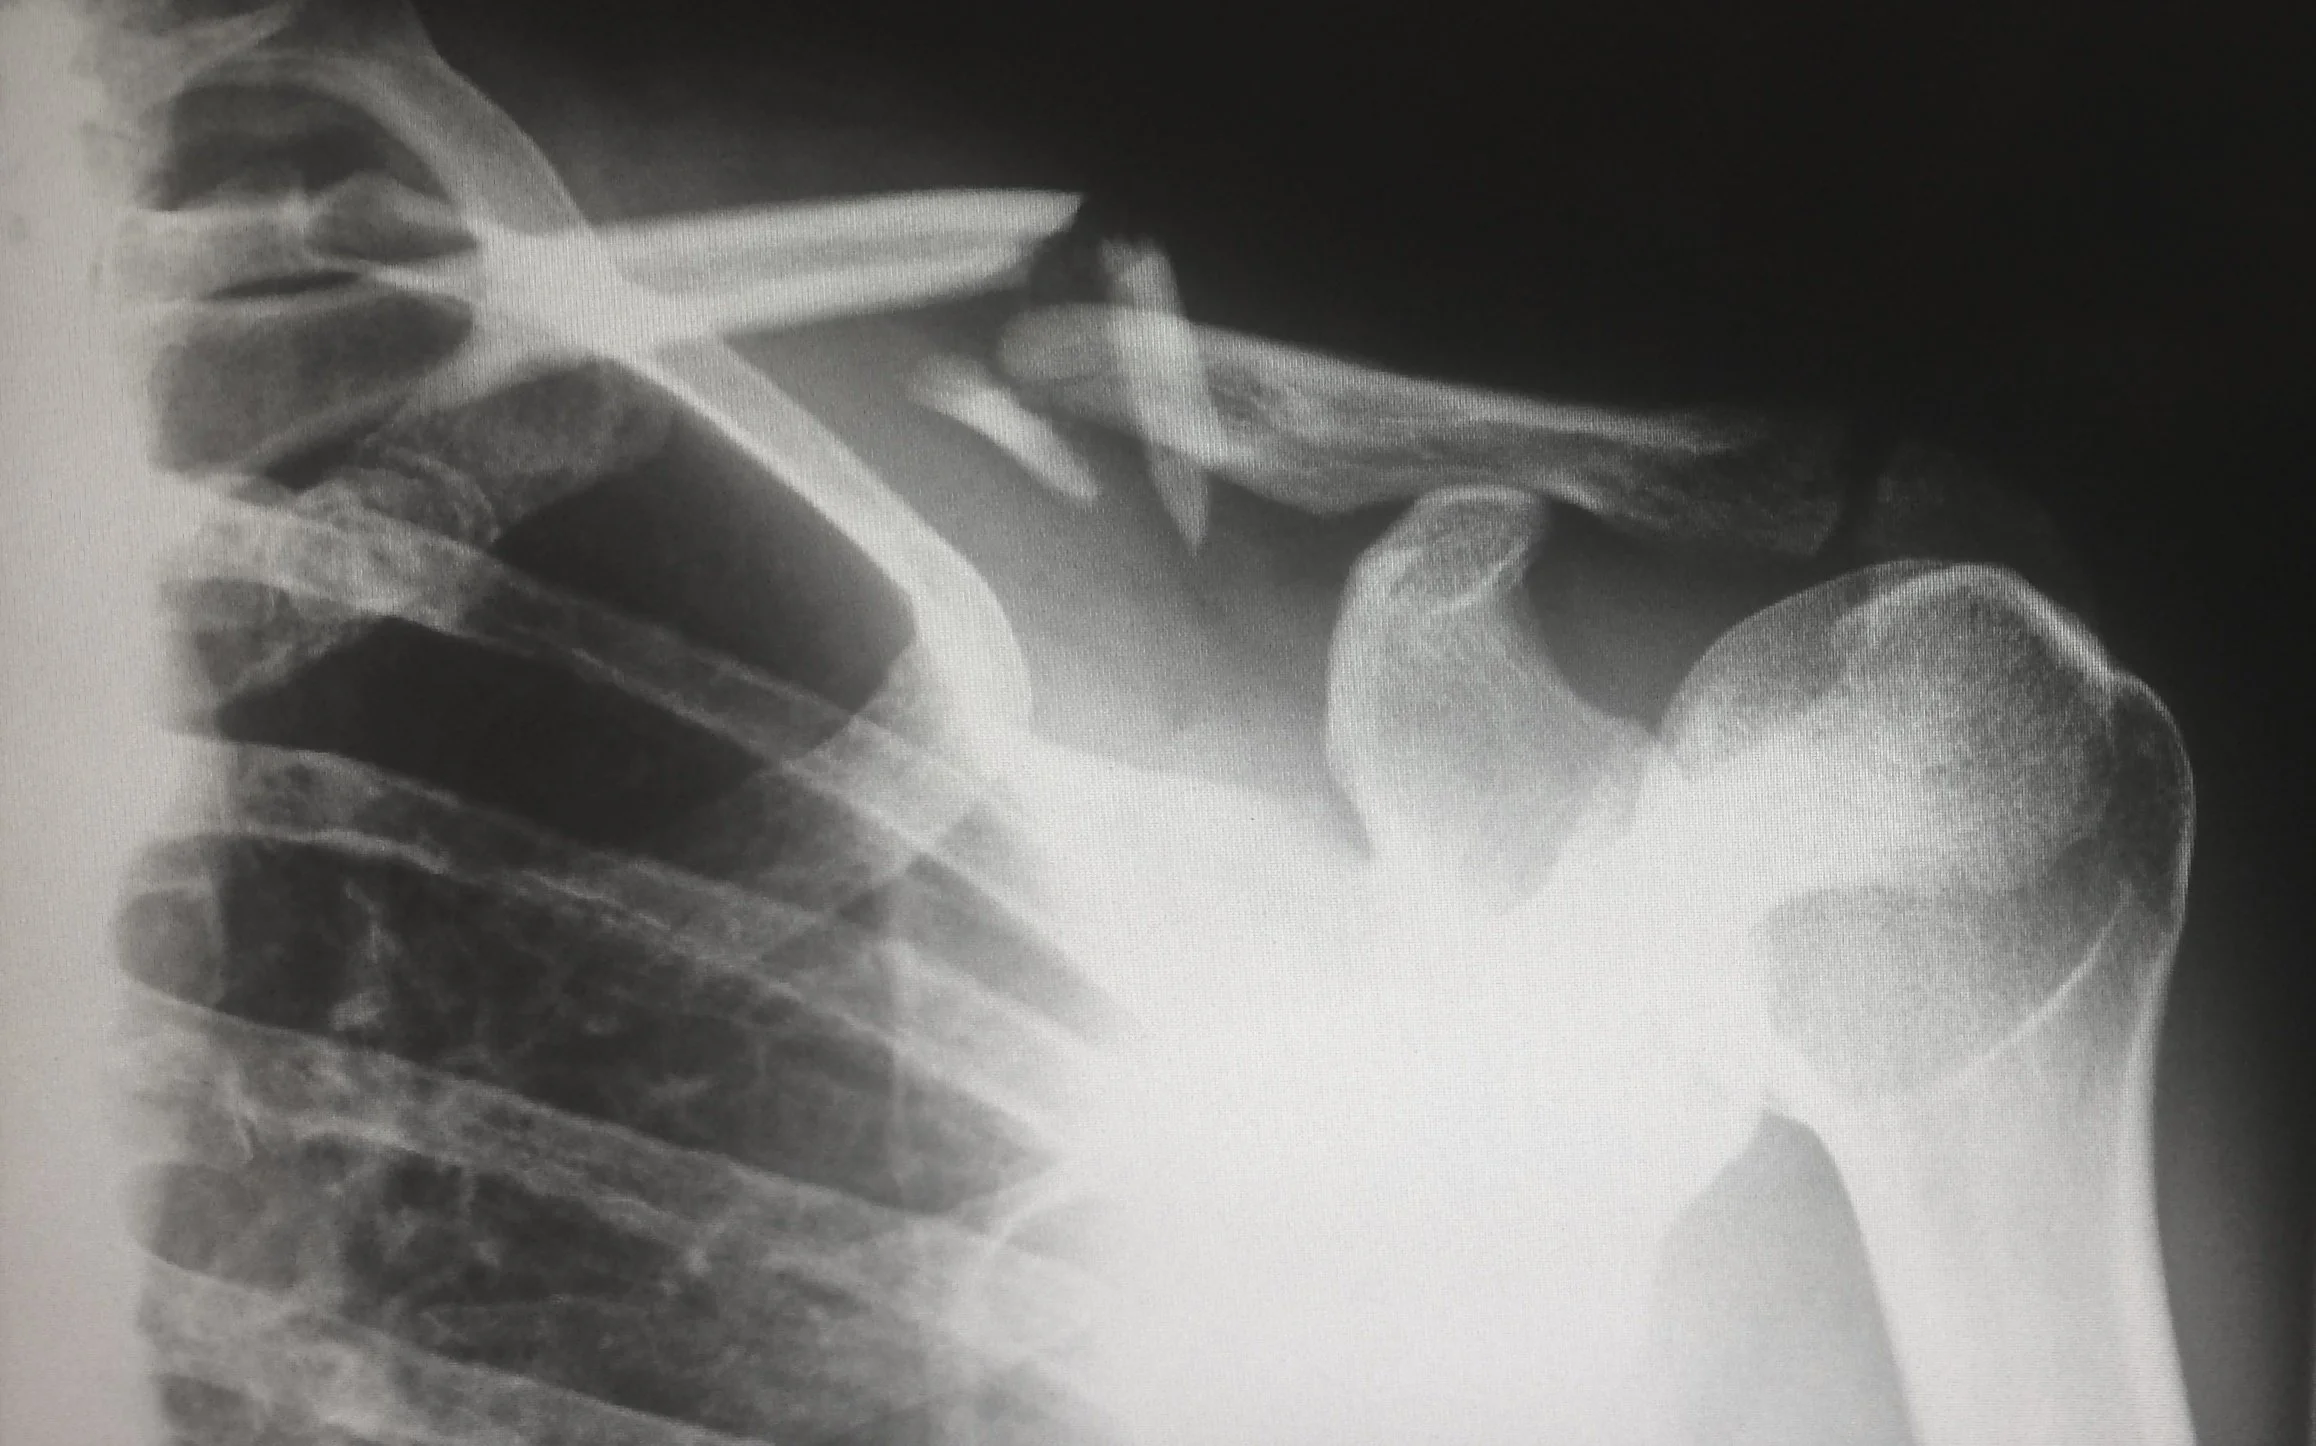

Shoulder Pain: Rotator Cuff Injuries and Treatment

Rotator cuff injuries are common, especially among athletes and people with physically demanding jobs. The rotator cuff can wear down as a result of repeated motion, which can cause injury to the shoulder.